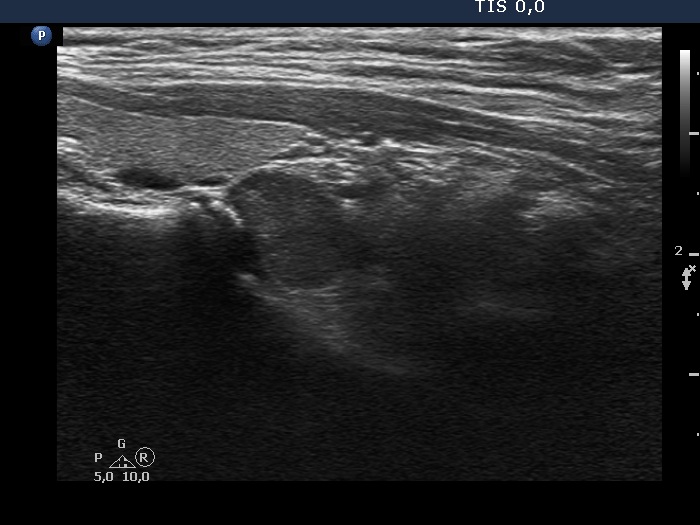

Right lobe, longitudinal scan

Lower part of the right lobe, longitudinal view. This lesion is located outside the thyroid, just under the lower pole.